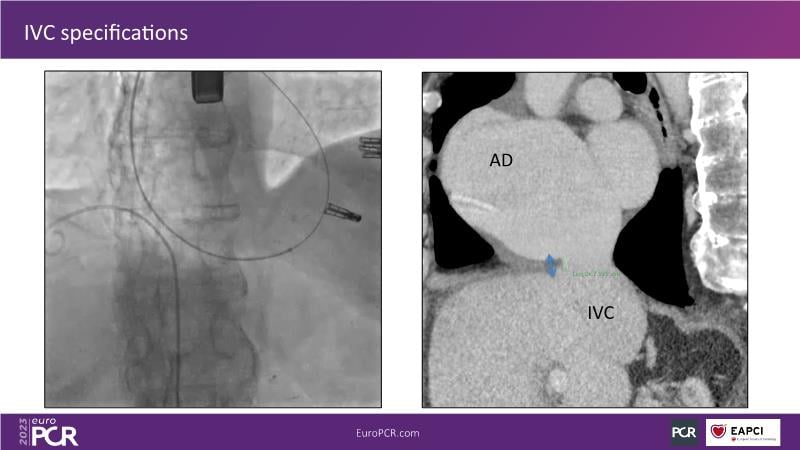

Heterotopic valve replacement for patients with right heart failure and tricuspid regurgitation - All you need to know!

Discover the comprehensive guide to heterotopic valve replacement for patients experiencing right heart failure and tricuspid regurgitation. Join this session to gain insights into patient selection criteria, delve into the concept behind this innovative procedure, and grasp the fundamental aspects of its execution.

- To understand the basics of the procedure